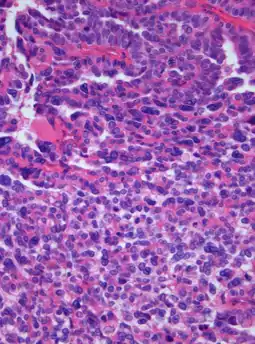

| Photomicrograph of hematoxylin-eosin stained section of a choroid plexus carcinoma (grade III WHO) at 400x magnification. | |